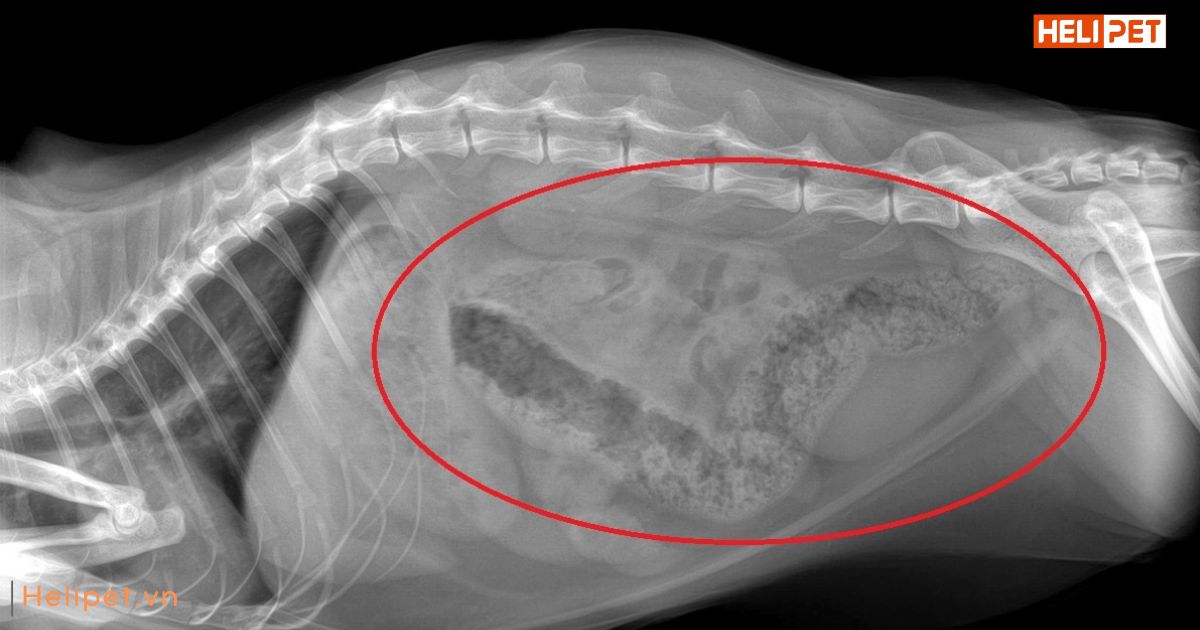

Hình ảnh mèo bị táo bón trên phim X-quang